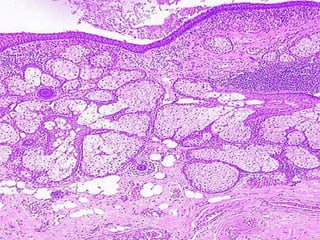

Hydatidiform Mole

• 1/1000 in USA

• 1% in Indonesia

• Also called NON-invasive mole in

its most common benign variant,

but can also be “invasive”

• Complete (2% chorioCA incidence)

or partial (0% incidence)

• Grapelike clusters, i.e., swollen villi

Hydatidiform Mole •1/1000 in USA • 1% in Indonesia • Also called NON-invasive mole in its most common benign variant, but can also be “invasive” • Complete (2% chorioCA incidence) or partial (0% incidence) • Grapelike clusters, i.e., swollen villi